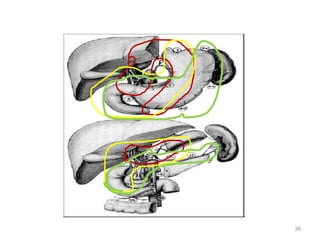

Stomach and Regional Anatomy– for

RT Planning

25

Stomach and Regional Lymph Nodes –

for RT Planning

26

Local

blood

supply

Which lymph nodes have to be included in the CTV?

• individualize for GE-junction/Cardia (proximal), Corpus (middle)

and antrum (distal) tumors

• GE-junction/Cardia/proximal 1/3: para-oesophageal, perigastric,

hepatogastro lig, perigastric, ,celiac (left gastric artery, celiac

axis), splenic hilum, suprapancreatic, porta hepatis,

pancreaticoduodenal [stations 1-4;7,9-13]

• Corpus/middle 1/3: perigastric, suprapyloric, infrapyloric, celiac

(left gastric artery, common hepatic artery and celiac axis),

splenic hilum, suprapancreatic, porta hepatis,

pancreaticoduodenal [stations 3-13]

• Antrum/distal 1/3: perigastric, suprapyloric, infrapyloric, splenic

artery, pancreaticoduodenal, porta hepatis, celiac (left gastric

artery, common hepatic artery and celiac axis), suprapancreatic

[stations 3-9;11-13] 35